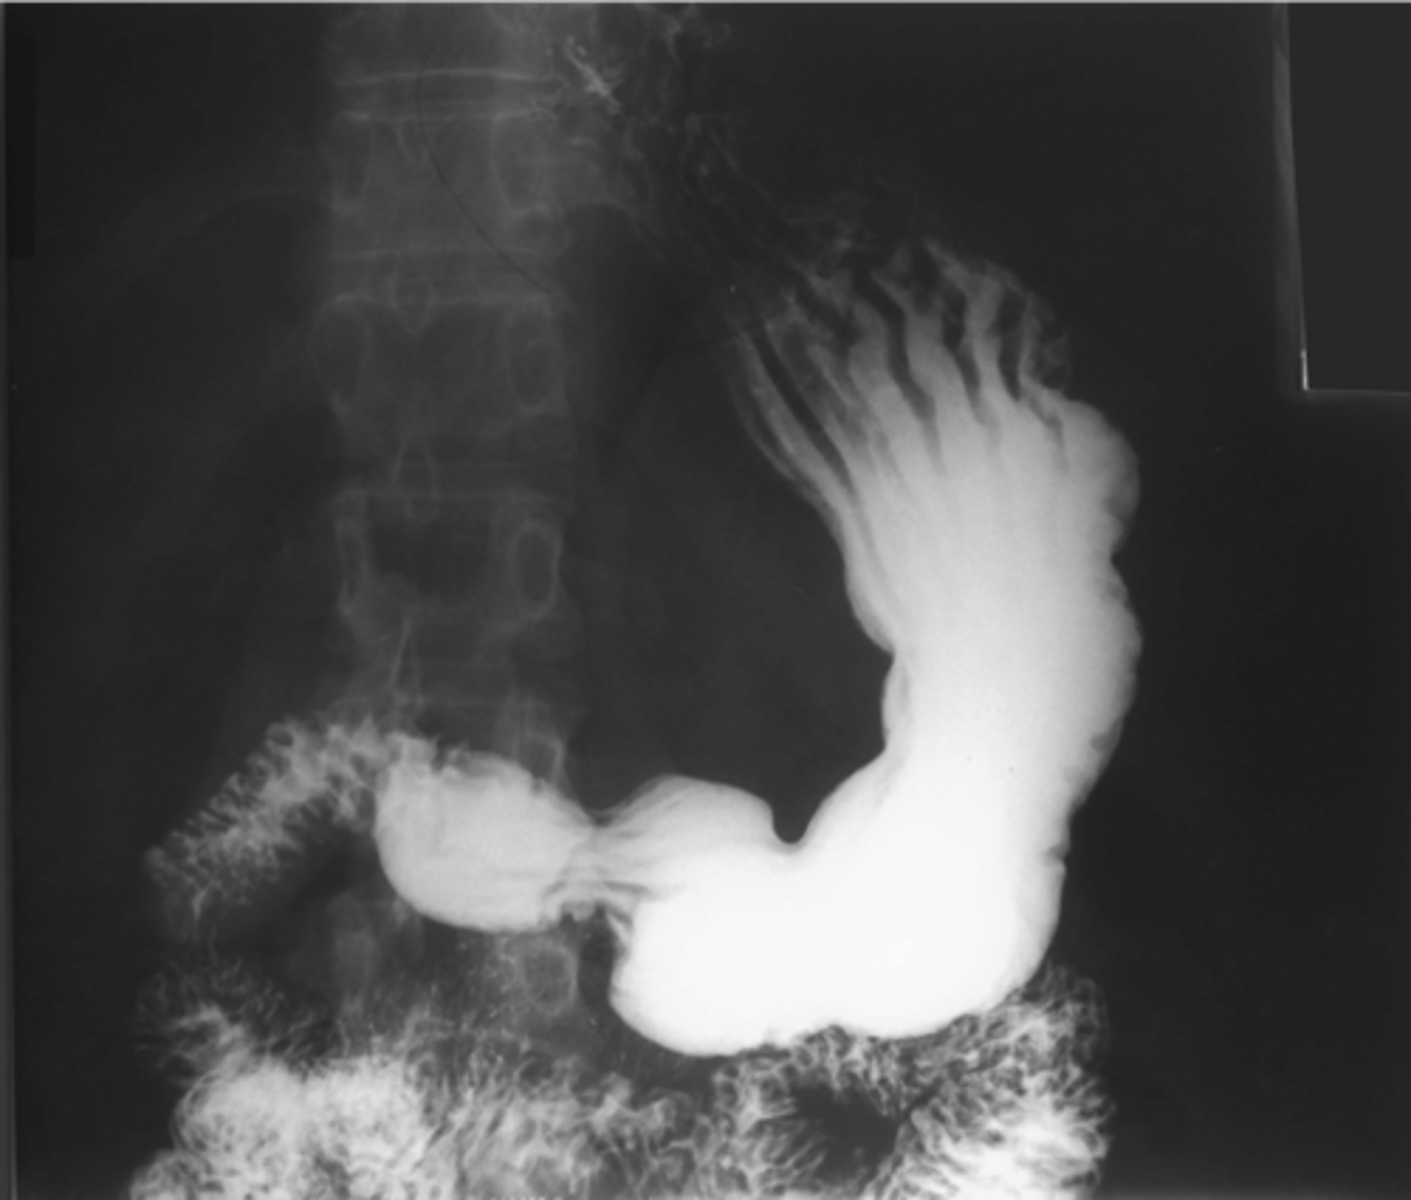

Normal colonic distension (barium enema study)

shows large bowel on barium swallow with follow through